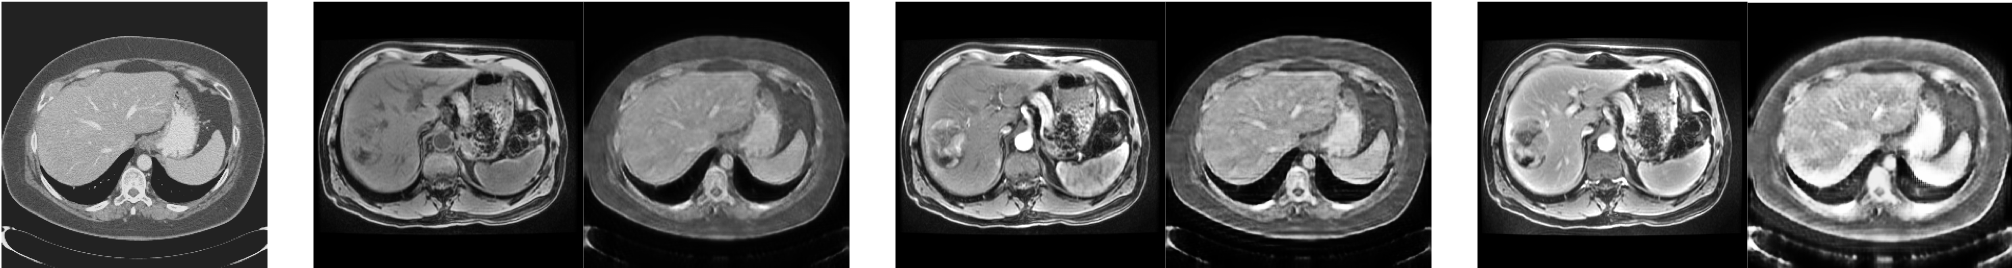

Refer to caption

Figure 1: Images and histograms of liver (yellow) and whole image (blue). From left to right: CT, multiphasic MRI sequence at three time points (pre-contrast, 20 seconds post-contrast i.e. arterial phase, 70 seconds post-contrast i.e. portal venous phase)

We tested our methods on unpaired CT slices of 130 patients from LiTS challenge 2017 [1] and multi-phasic MRI slices of 20 local patients with HCC (see Fig. 1). CT and MR were divided into 5 folds for subject-wise cross-validation. A supervised UNet [10] trained and tested on pre-contrast MR serves as upper bound of domain adaptation, while a supervised UNet trained on CT and tested on pre-contrast MRI, without domain adaptation, provides the lower bound, which shows the relatively large domain shifts between CT and MRI (see Table 2).